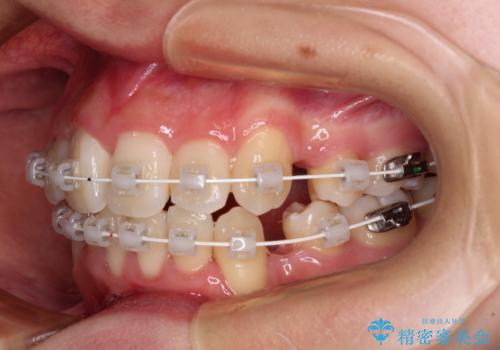

- 上下前歯の八重歯やデコボコと、唇の閉じにくさを気にして来院された患者様です。

口元の突出感を改善するため、上下左右の第一小臼歯4本を抜歯し、ワイヤー装置にて矯正治療を行うこととしました。

デコボコの解消で歯が磨きやすくなり、抜歯矯正により口元の突出感が大幅に改善され、スッキリした口元になりました。